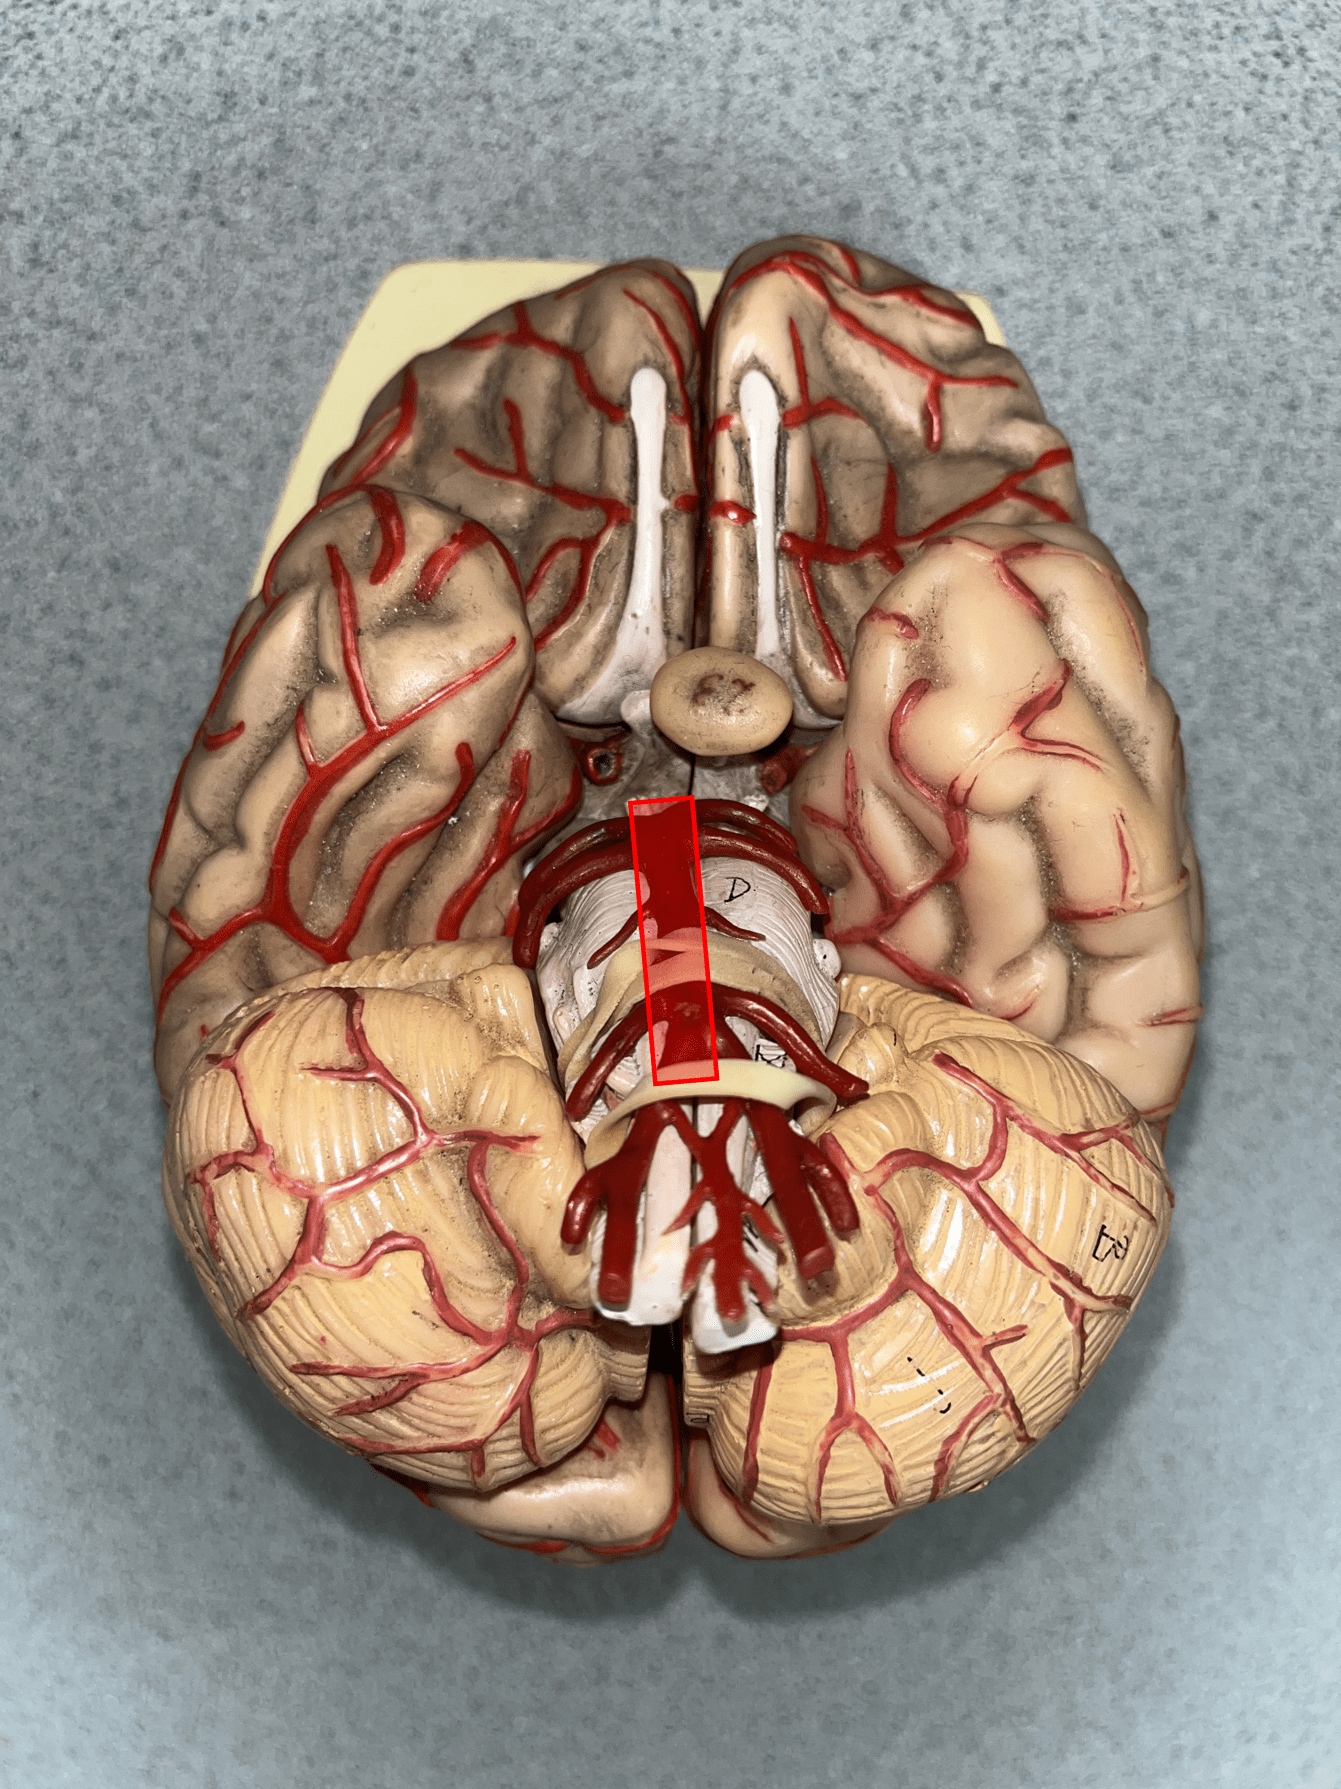

anterior cerebral artery

• An artery of the cerebral circulation.

• Originates from the internal carotid artery.

• Supplies the frontal and parietal lobes of the brain.

• Originates from the internal carotid artery.

• Supplies the frontal and parietal lobes of the brain.

posterior communicating artery

• An artery of the cerebral circulation (not shown).

• Connects the posterior cerebral and internal carotid arteries.

• Connects the posterior cerebral and internal carotid arteries.

posterior cerebral artery

• An artery of the cerebral circulation.

• Originates from the basilar artery.

• Supplies the temporal and occipital lobes, midbrain, and thalamus.

• Originates from the basilar artery.

• Supplies the temporal and occipital lobes, midbrain, and thalamus.

basilar artery

• An artery of the cerebral circulation.

• Originates from the convergence of the vertebral arteries.

• Supplies the cerebellum, pons, and inner ear through its branches.

• Originates from the convergence of the vertebral arteries.

• Supplies the cerebellum, pons, and inner ear through its branches.

superior sagittal sinus

• A vein of the cerebral circulation.

• Drains the superficial brain.

• Empties into the internal jugular vein.

• Drains the superficial brain.

• Empties into the internal jugular vein.

inferior sagittal sinus

• A vein of the cerebral circulation.

• Drains the deep brain.

• Empties into the internal jugular vein.

• Drains the deep brain.

• Empties into the internal jugular vein.